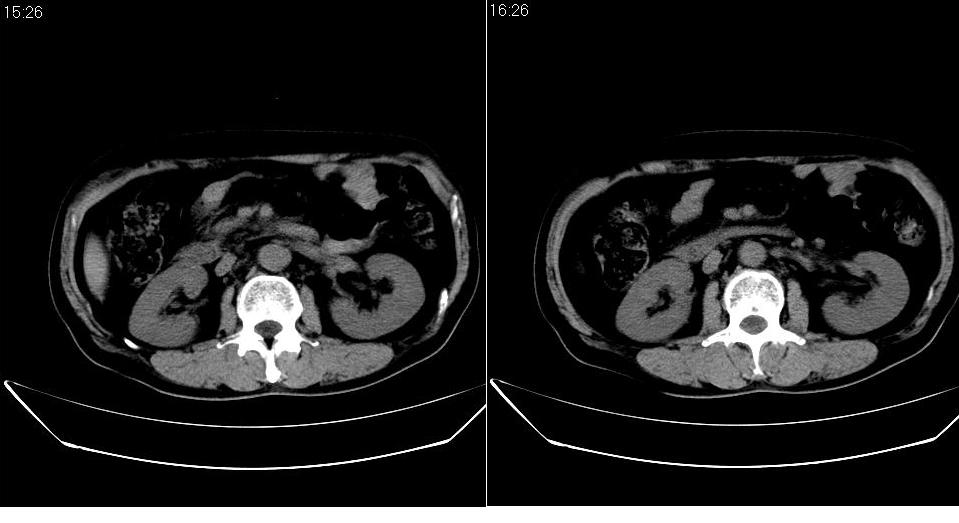

男 48岁,09年8月份在上级医院确诊胰头癌,准备在我院化疗。

胰头体积增大内见低密度影考虑为占位,肿瘤性病变可能性大。

胰头体积增大,外形不规则,密度欠均,支持胰头癌可能性大。